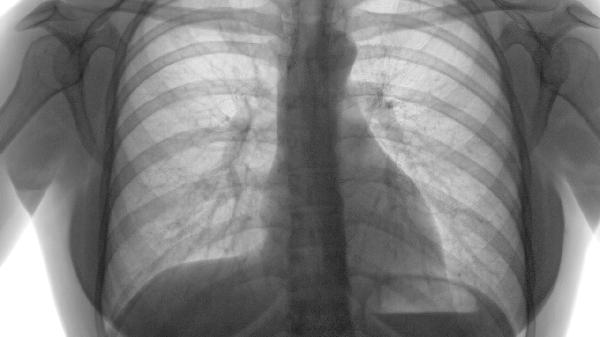

肺气肿是慢性阻塞性肺疾病的主要亚型,特征为终末细支气管远端气腔异常扩大伴肺泡壁破坏。根据全球慢性阻塞性肺病倡议指南,其严重程度分为轻度、中度和重度三级,是否属于"大病"需根据肺功能检测中FEV1占预计值百分比、症状频率及急性加重次数综合评估。

当FEV1<50%预计值且合并二氧化碳潴留时,可能发展为慢性呼吸衰竭、肺源性心脏病。患者需家庭氧疗或无创通气支持,每年住院次数增加,此时被纳入医保特殊慢性病管理目录,属于明确的大病范畴。

约5%患者会进展为巨大肺大疱或自发性气胸,需胸腔镜手术干预。这类急重症情况虽发生率低,但可能危及生命,属于呼吸科急危重症诊疗范围。